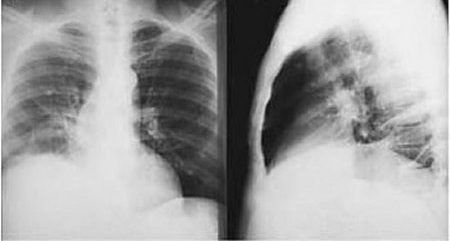

CXR

Test

Performed if clinical findings suggestive of effusion and presence of liver abscess. [Figure caption and citation for the preceding image starts]: Posterior-anterior and lateral CXR of a patient with amoebic liver abscess: CXR findings include elevated right hemidiaphragm and evidence of atelectasisReproduced from New England Journal of Medicine (2003); used with permission [Citation ends].

Result

right hemidiaphragm elevation or right-sided pleural effusion